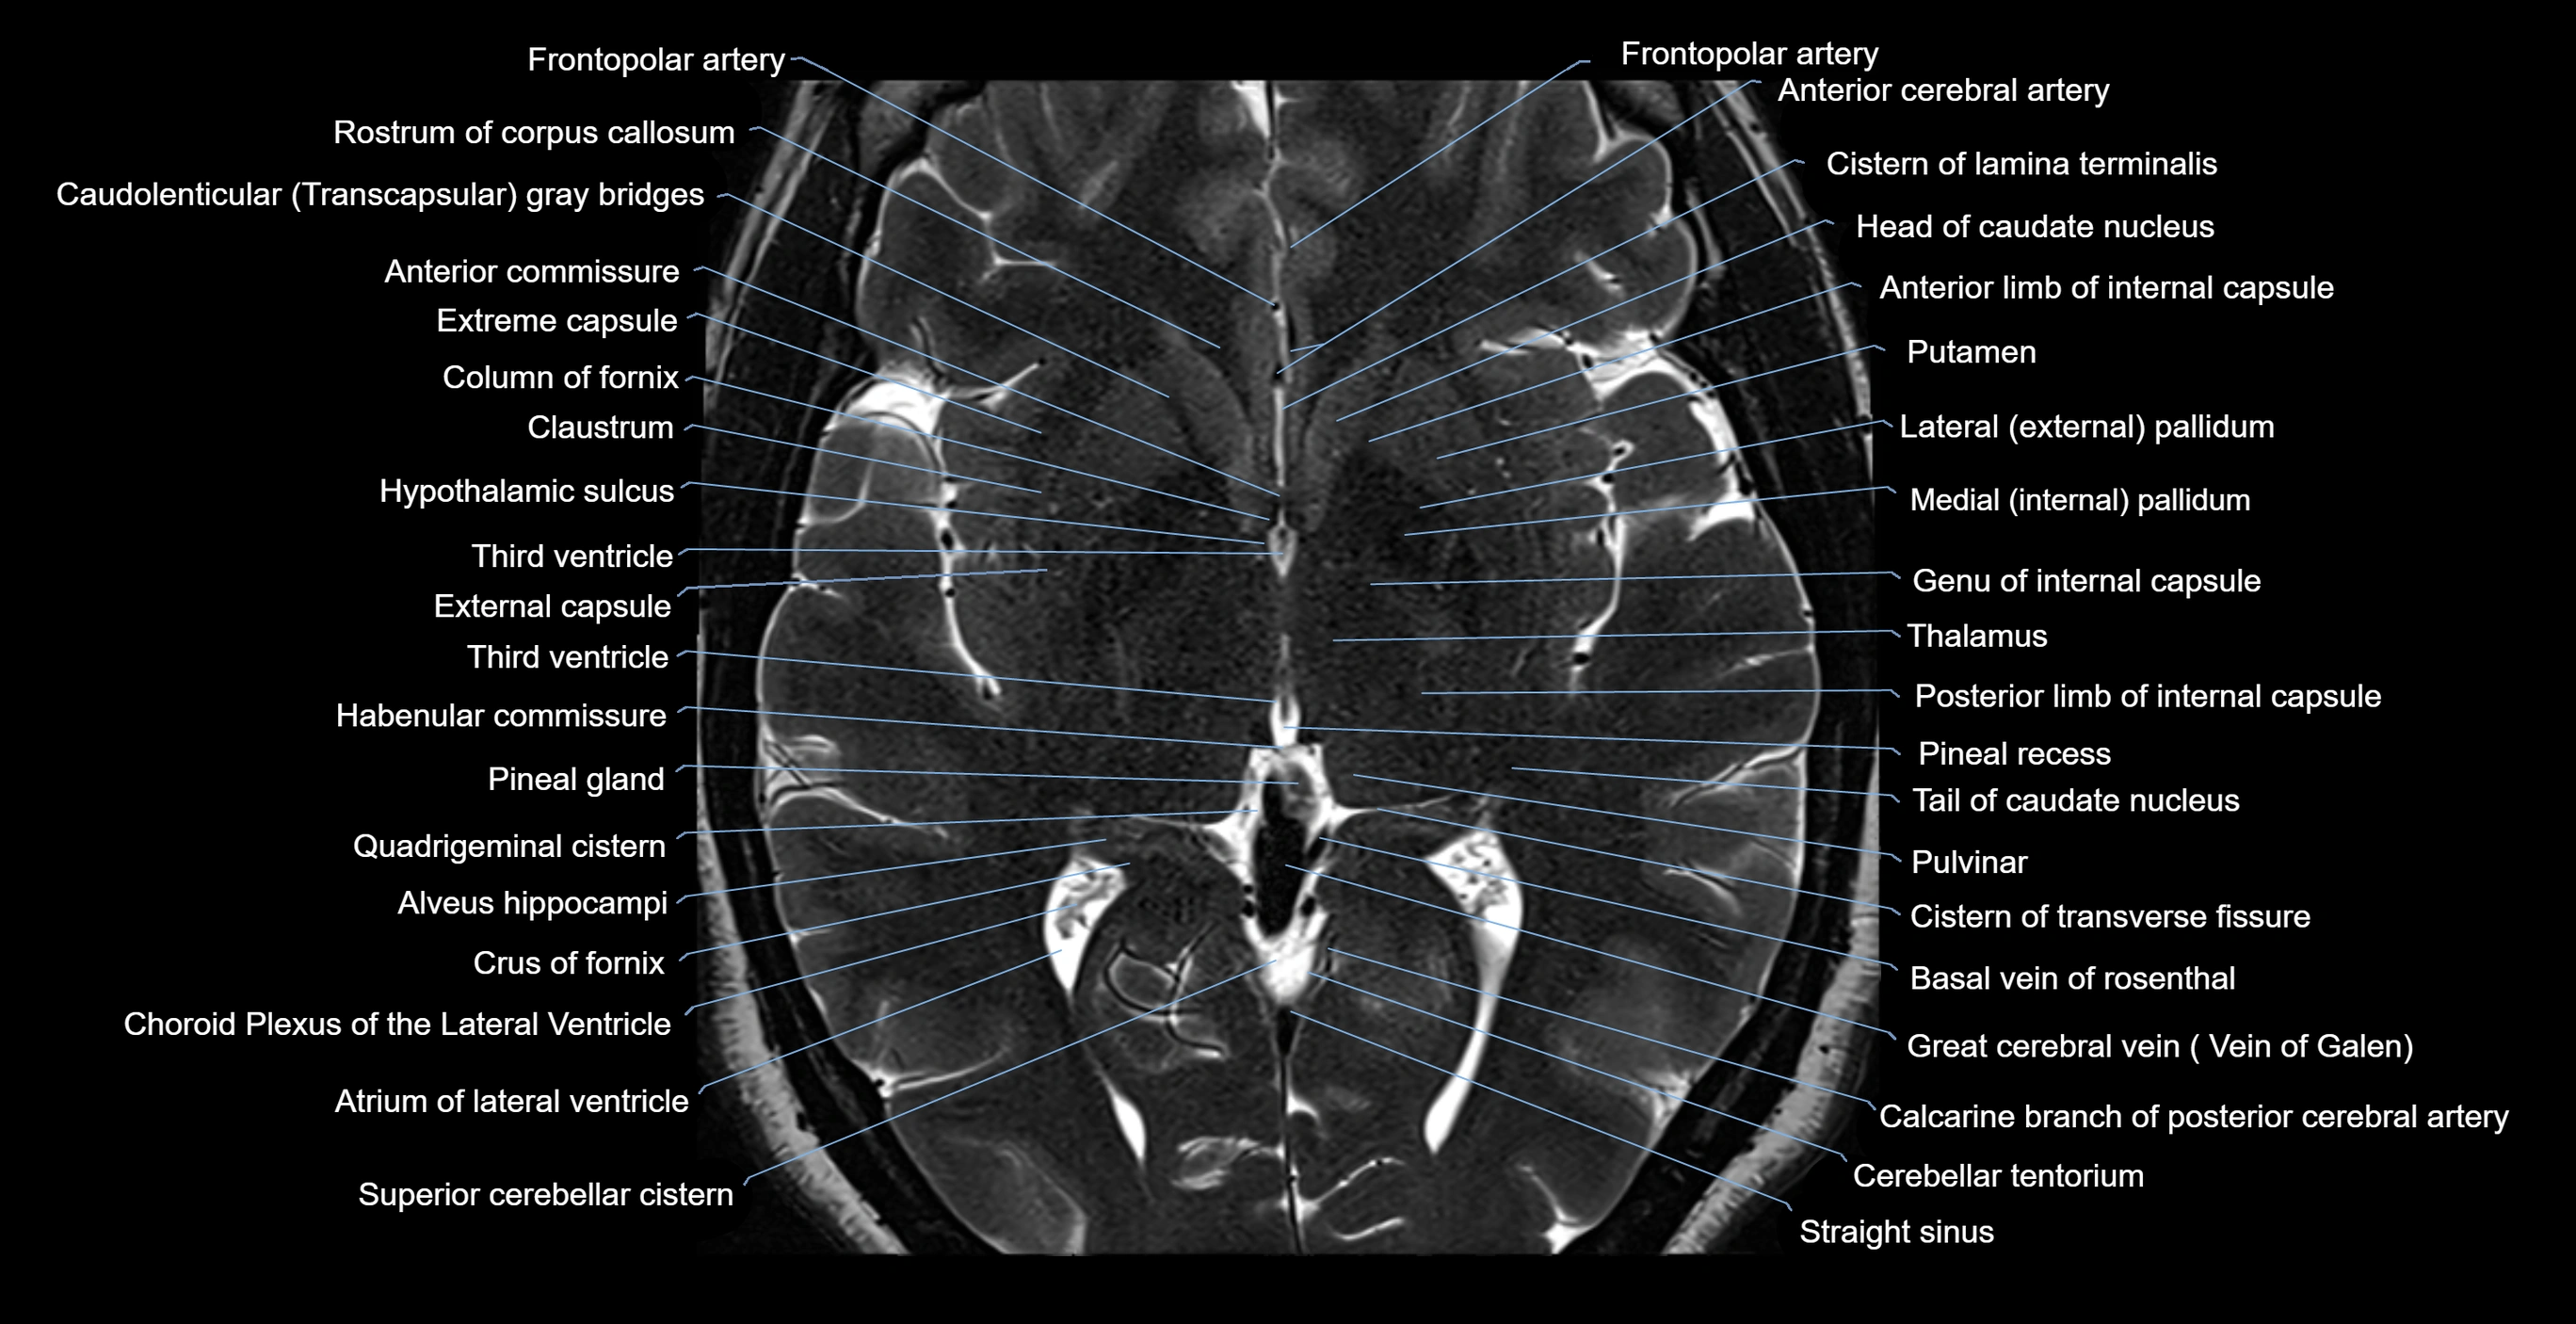

- Anterior commissure

- Anterior limb of internal capsule

- Atrium of lateral ventricle

- Basal vein of rosenthal

- Body of caudate nucleus

- Body of fornix

- Calcarine branch of posterior cerebral artery

- Cerebellar tentorium

- Choroid plexus of the lateral ventricle

- Cistern of lamina terminalis

- Cistern of transverse fissure

- Claustrum

- Column of fornix

- Crus of fornix

- External capsule

- Extreme capsule

- Frontopolar artery

- Great cerebral vein

- Habenular commissure

- Head of caudate nucleus

- Hypothalamic sulcus

- Infundibular recess

- Lateral pallidum

- Medial pallidum

- Occipital horn of lateral ventricle

- Pineal gland

- Pineal recess

- Posterior limb of internal capsule

- Pulvinar

- Putamen

- Quadrigeminal cistern

- Rostrum of corpus callosum

- Straight sinus

- Tail of caudate nucleus

- Thalamus

- Third ventricle

- genu of internal capsule